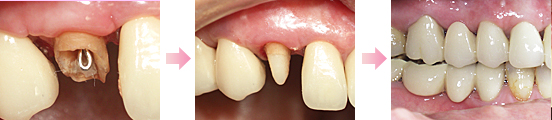

オールセラミックス(ジルコニア)110,000円~132,000円(税込)

金属を使わないセラミックスだけでできたかぶせものです。より自然な色あいと形を再現します。永年の使用にも変色せず、健康的な白い歯の輝きで天然歯の美しさを保ちます。

電鋳メタルボンド110,000円(税込)

メッキの技術を応用して、より精密なかぶせものを純金で作り、その上からセラミックスを焼き付けています。金属部分が純金ですから、歯茎との境目に気になる黒ずみが出にくく、明るく仕上がります。